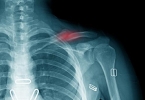

1、外伤后遗症:如果曾经有过脚踝的外伤,可能会导致软组织损伤或骨折未完全愈合,从而引发疼痛和功能障碍。物理疗法如热敷、按摩以及针对性的运动康复训练可以帮助缓解症状。